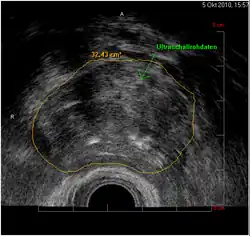

HistoScanning-Befund: 3-dimensionales Bild der zusammengesetzten Querschnitte. Tumorausdehnung rechte Prostatahälfte (grün). Linksseitig kaum Tumor, somit Nervenerhalt möglich.

Bei Ultraschallbildgebungsverfahren werden die gewonnenen Ultraschalldaten umgesetzt in Grautöne, um so ein Bild zu erzeugen und vorhandene Strukturen zu visualisieren. HistoScanning ist kein Ultraschallbildgebungsverfahren, sondern Ultraschall wird lediglich quasi als „Werkzeug“ eingesetzt. Idee der Entwickler war, eine KI auf die Erkennung von Prostatakrebs zu trainieren, indem man sie mit Sonografiedaten und dazu korrespondierenden Gewebeschnitten füttert. Der Trainingsdatensatz bestand aus den Daten von 14 Patienten, deren Prostata operativ entfernt und vollständig histologisch aufgearbeitet worden war. Der Schallkopf liegt im Enddarm und scannt die Prostata vollständig ab. Drei Algorithmen berechnen Zelldichte, Heterogenität, und Vaskularisierung, und überlagern diese Parameter dem Ultraschallbild farbig.